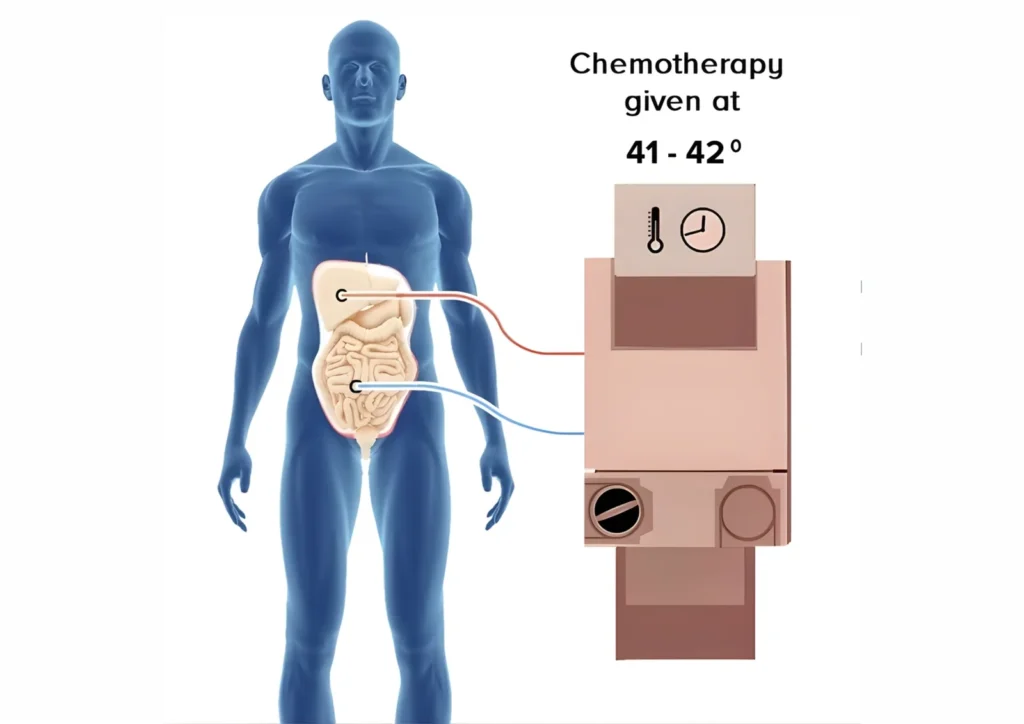

Heated Chemotherapy Circulation

Chemotherapy solution heated to 41–43°C

Circulated within the abdomen for 60–90 minutes

Continuous movement ensures uniform drug distribution

Heat enhances chemotherapy effectiveness by damaging cancer cells and increasing drug penetration.